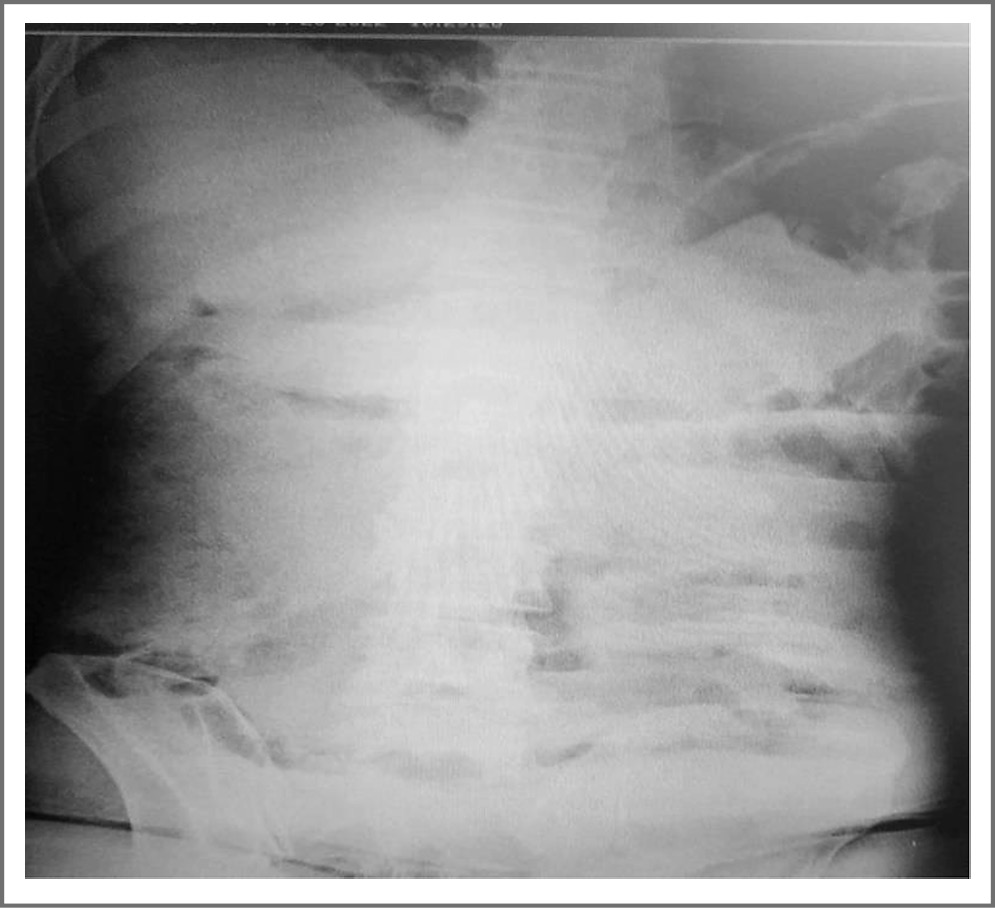

Осмотрен хирургом, однако данных в пользу острого хирургического процесса не выявлено. Горизонтальных уровней жидкости, свободного газа в брюшной полости на рентгенограмме не выявлено (рис. 2).

Рис. 2. Рентгенограмма органов брюшной полости больного М. / Fig. 2. Radiograph of the abdominal organs of patient M.

Затем на УЗИ органов брюшной полости заподозрена толстокишечная непроходимость (петли толстого кишечника раздуты, маятникообразное движение).